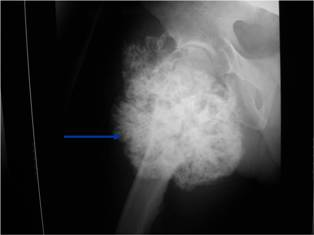

Plain X-ray: Secondary Chondrosarcoma of Proximal Femur

Radiographic Presentation

Plain X-rays:

- Projects from bone with narrow (pedunculated) to broad (sessile) stalk

- Corticomedullary continuity: Medullary bone continuous with that of osteochondroma and cortex blends with that of osteochondroma

- Calcification in cartilaginous cap (“Ring and Arc” and stippled calcifications)

- Lobular growth pattern